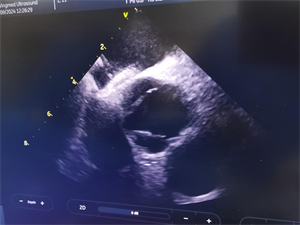

经我院心血管内科充分的病例讨论后,行右心声学造影排查以及经食道心脏超声的进一步证实,终于找到了疾病的“元凶”——卵圆孔未闭。在与患者及家属进行细致的沟通及充分的术前准备。心血管内科介入团队与超声科通力合作,为患者成功进行了卵圆孔未闭介入封堵手术。术后,患者在医护人员的精心照料下恢复良好,现已康复出院。

2.经食管超声心动图(诊断卵圆孔未闭的金标准和首选方法)